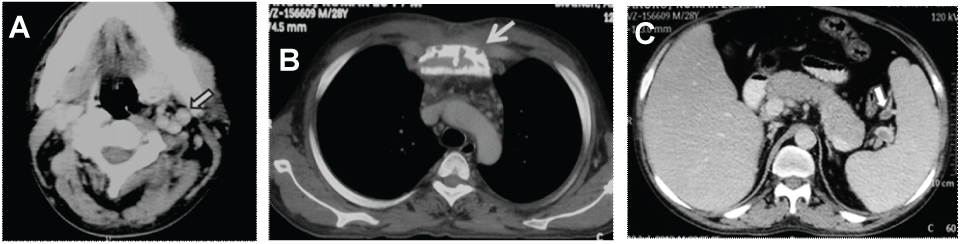

A 28-year-old male patient presented with history of progressive weakness of bilateral lower limbs for the last eight months. He had previous history of febrile illness and diarrhea followed by motor weakness of left lower limb with no sensory deficit. One month later right lower limb was also involved following which he developed weakness in bilateral upper limbs after six months. There was no history of bladder or bowel disturbance. There was no past history of any prolonged illness. There was no significant family history. On detailed physical examination patient was found to have oedema over bilateral leg, generalized clubbing, patchy redness over anterior chest wall [Table/Fig-1a-c] in midline, flushing over face, papilloedema and decreased tone in both upper and lower limbs with reduced deep tendon reflexes. He was also found to have bilateral axillary lymphadenopathy. Neurological examination supported evidence of motor demyelinating neuropathy. Non selective bone marrow aspirate showed 6% monoclonal plasma cells with plasma cells clumps. Biopsy from the right axillary lymph node was suggestive of hyaline vascular type of Castleman’s disease. Serum electrophoresis was positive for Myeloma protein and CSF analysis revealed high protein levels. Endocrine evaluation including TSH, cortisol, LH and FSH were within normal limit. These constellation of findings including polyradiculoneuropathy, lower limb oedema, skin changes, papilloedema, polycythemia, monoclonal plasma cell disorder and lymph node biopsy revealing Castleman’s disease, guided the oncologist to make the diagnosis of POEMS syndrome. Contrast enhanced CT was done in the Department of Radiology, BRAIRCH at All India Institute of Medical Sciences, New Delhi, India. The CECT showed hepatosplenomegaly along with discrete homogenous cervical, axillary and retroperitoneal lymphadenopathy [Table/Fig-2a]. There was focal solitary mildly expansile lytic- sclerotic lesion of sternum with cortical breech [Table/Fig-2b]. The other predominant finding was evidence of partial thrombosis in tributaries of splenic vein at the hilum [Table/Fig-2c]. The patient was started treatment with high dose chemotherapy which included corticosteroids and melphalan. However, the patient died with renal failure being the preterminal event.

Axial CECT showing (a) enlarged enhancing lymph nodes (closed arrow) in neck, (b) mixed lytic sclerotic lesion in sternum (arrow) and (c) hepatosplenomegaly with splenic vein thrombosis (closed arrow)